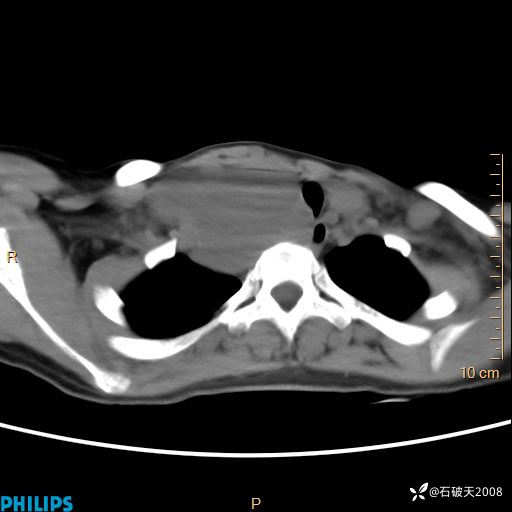

静脉期